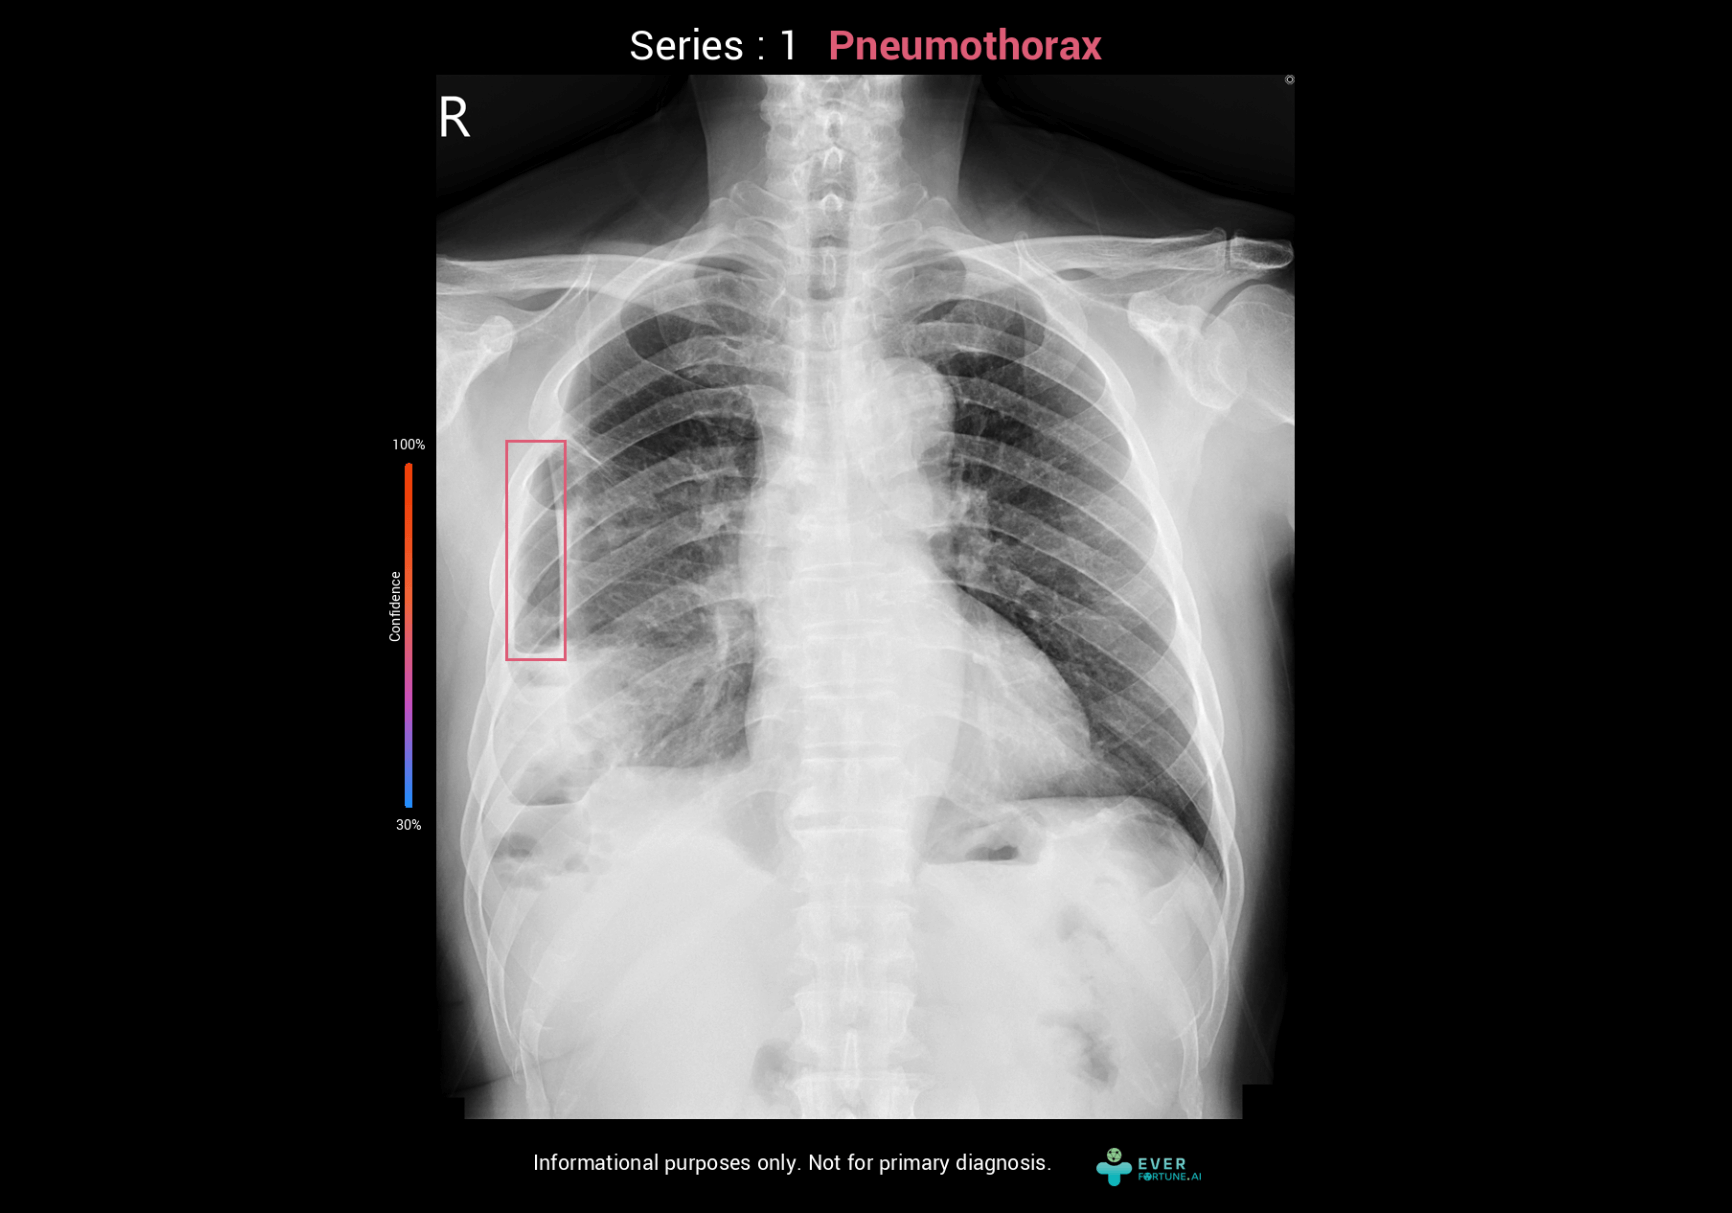

Pneumothorax Assessment System

ChestSuite XR Assessment System

Identify 15 abnormal finding in chest X-ray images with heart, lungs and bones. The system as a pre-read assistance enable a quick interpretation and faster decisions